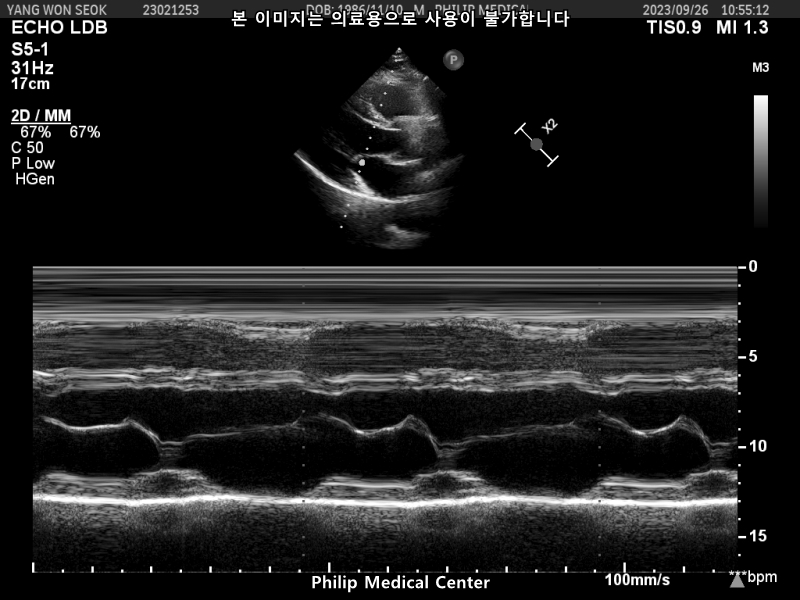

심장초음파는 경미한 폐동맥 판막역류소견과 심전도 검사결과 비특이적 ST-T파 이상소견이있었습니다.

• 1번 째 사진